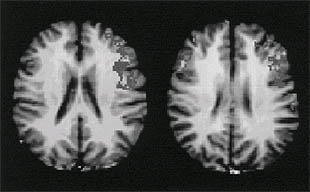

foto de la noticia

Una serie divulgativa española explora los misterios de la ciencia

¿Es infinito el universo? ¿Se podrán predecir fiablemente los terremotos? ¿Cómo surgió la vida? Éstas son algunas de las cuestiones que tratará de responder Futuro, una serie española de divulgación científica cuyo rodaje acaba de comenzar. Constará de ocho capítulos de 52 minutos, producidos por New Atlantis, Media Park y Quiero.